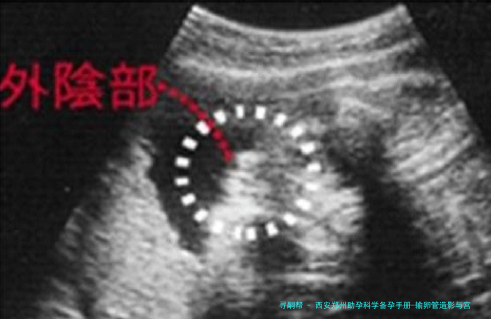

输卵管造影是一种评介输卵管通顺度的影像学检查。它并非将器械深入宫腔,而是通过宫颈向子宫腔体内注入造影剂,然后利用X光或超声技术,即时察看造影剂是否能够顺利通过输卵管并扩散至盆腔,进而评价输卵管是否通畅、阻塞的部位以及子宫腔的样子。

主要目的:其主要功能是诊断输卵管是否通畅,以及是不是存留堵塞、积水或粘连等等问题。它是不育症病因筛查中的重要一环,尤其适合于怀疑因输卵管因素导致不孕的女性。